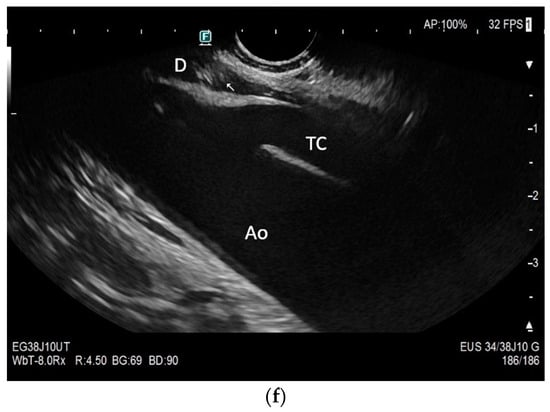

Subxiphoid: The diaphragm can be positioned directly subxiphoidally with a slightly sagittal transducer position on both sides next to the attachment to the sternum. The diaphragm limb can be demarcated to the right in the epigastrium in cross section between the aorta and the inferior vena cava. However, this is primarily of differential diagnostic importance, e.g., in relation to lymphomas, not for the actual assessment of the diaphragm (Figure 6).